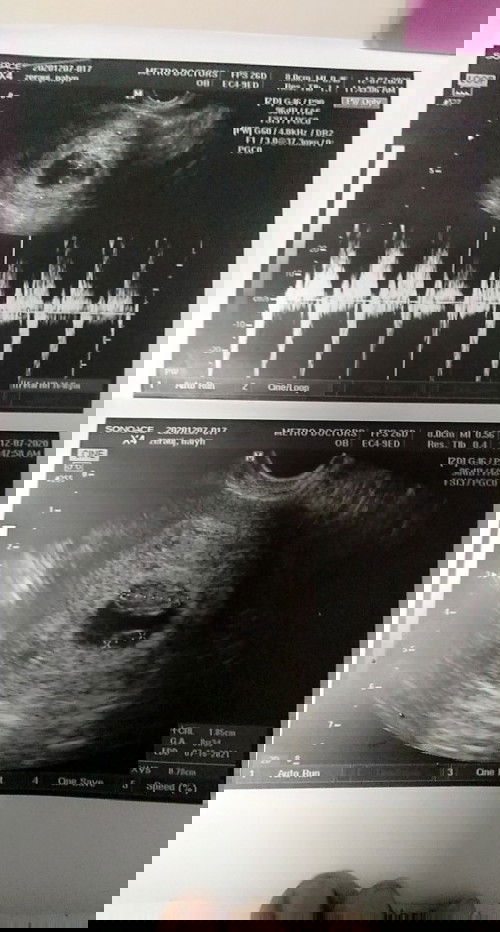

Hi to all mommy ask q lng poh cno marunong 2mingin ng ultrasound pic..ok lng kya baby q?

Ndi p kc nbsa ng doctor ultrasound q

I'm bleeding 5days

I'm worried